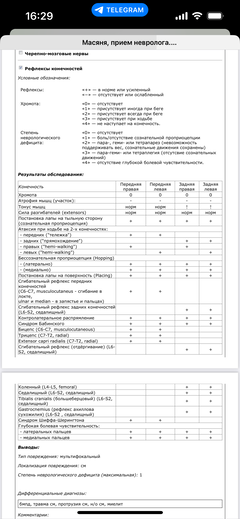

Ярко выраженная болезненность в области крестца, на обезболе полегче. По результатам приема невролога проведена миелография - множественная компрессия, возможно опухоль, возможно грыжа, нужно удалять...